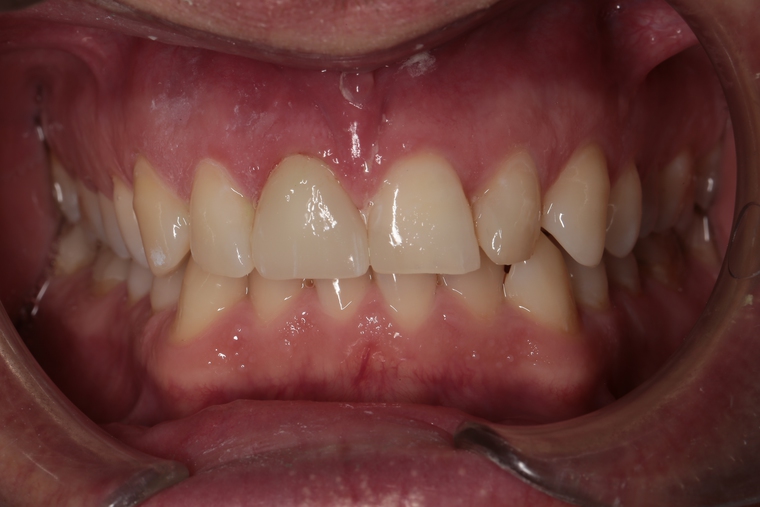

Ein Tätigkeitsschwerpunkt unserer Praxis in Salzburg ist die Implantologie. Wenn ein Zahn fehlt oder entfernt werden muss, sollte immer die Möglichkeit der Implantation im Vordergrund stehen. Ein Implantat verhält sich von den Eigenschaften genau so wie ein natürlicher Zahn. Egal ob nur ein einzelner Zahn vom Zahnarzt ersetzt werden muss oder ein ganzer Kiefer mit festsitzendem Zahnersatz versorgt werden soll, wir finden für Sie eine Möglichkeit, auch wenn die Voraussetzungen ausweglos erscheinen. Wenn möglich versorgen wir unsere Patienten mit Keramikimplantaten. Diese sind immun-neutral und können sehr oft direkt bei der Zahnextraktion eingesetzt werden. Für unsere Patienten ist daher meist nur ein operativer Eingriff notwendig!

- Eigenes Meisterlabor und persönlicher Zahntechniker für Ihre Arbeit